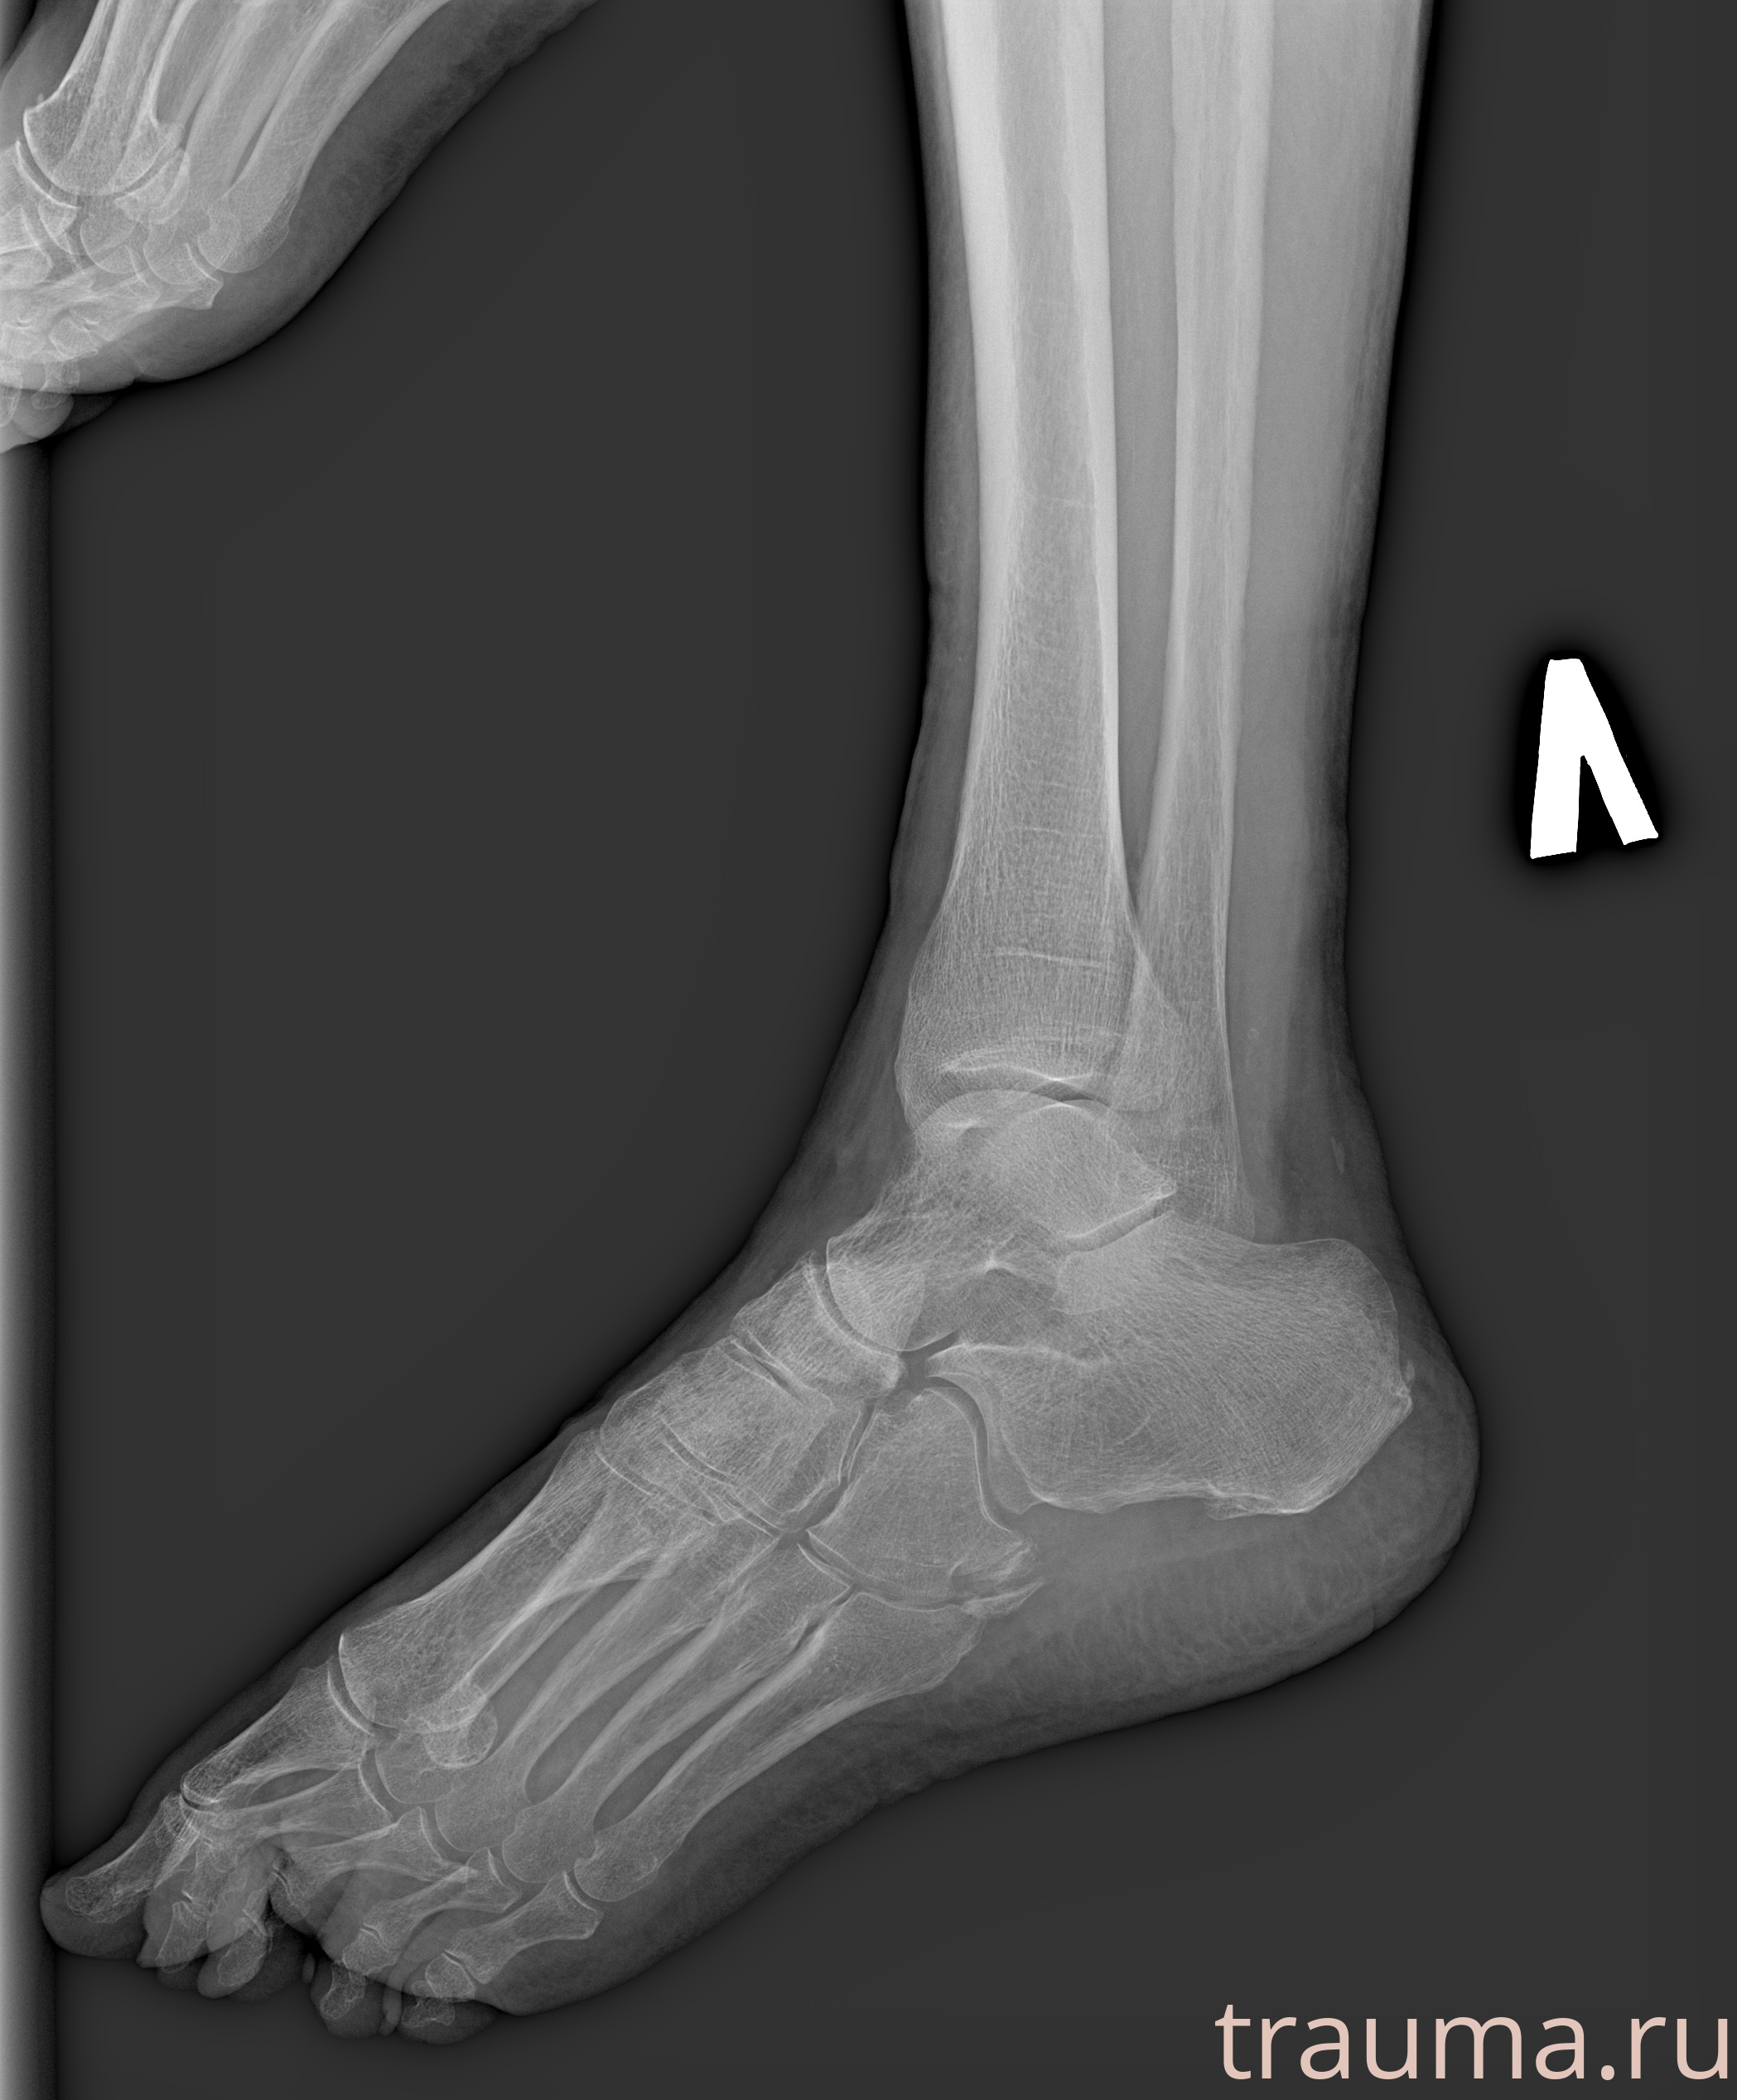

Рентгенограммы

Рентген на дому: по вашему адресу приезжает врач-рентгенолог, травматолог-ортопед с мобильным рентгеновским аппаратом, проводит диагностику травмы или заболевания, делает необходимые рентгенограммы, дает рекомендации по дальнейшему лечению. Получить качественные снимки в домашних условиях возможно благодаря уникальной методике, разработанной МосРентген Центром для института  Склифосовского